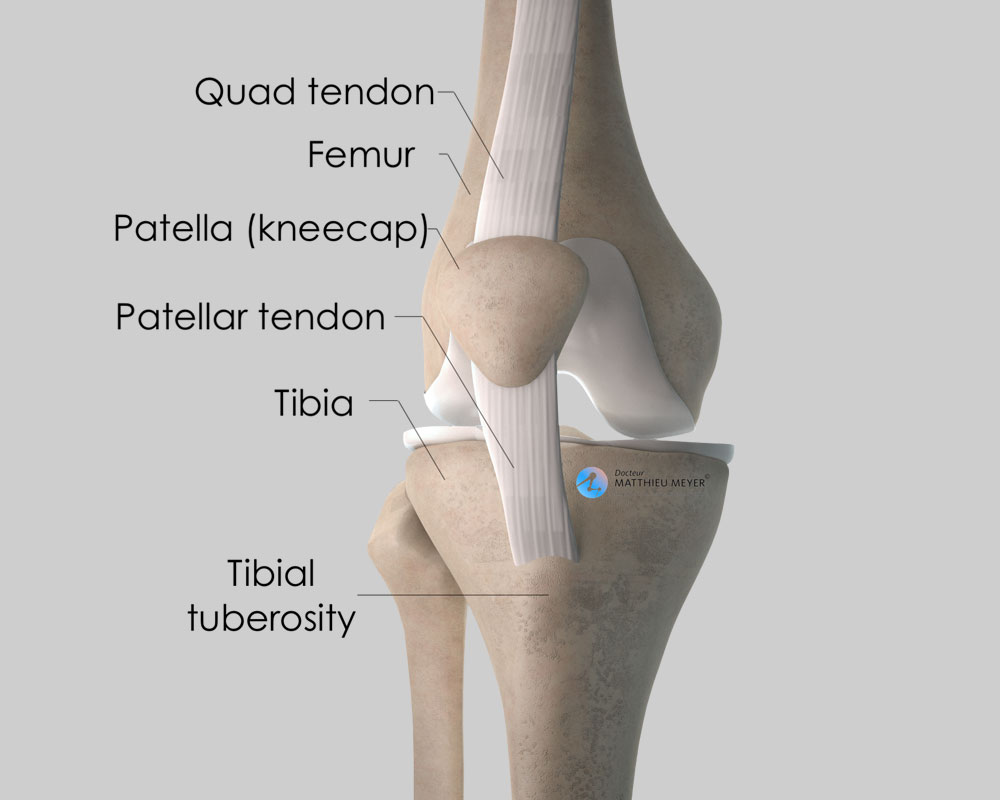

intercondylar eminence

styloid process